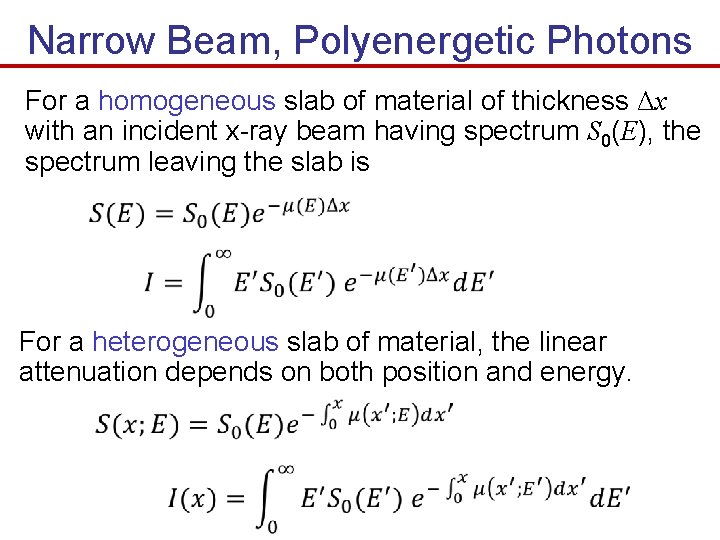

Narrow Beam, Polyenergetic Photons For a homogeneous slab of material of thickness Δx with an incident x-ray beam having spectrum S 0(E), the spectrum leaving the slab is For a heterogeneous slab of material, the linear attenuation depends on both position and energy.